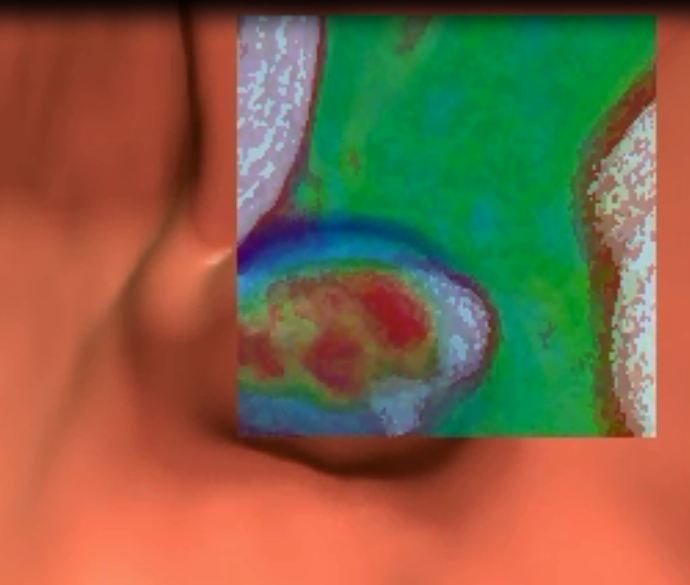

Virtual colonoscopy is a non-invasive, outpatient procedure that takes standard CT images of the abdomen while special software converts those images into a three-dimensional moving picture of the inside of the colon. A specially trained radiologist uses these images to look for polyps or abnormalities.

Virtual colonoscopy has been shown to be an effective examination in detecting clinically significant colon polyps and cancers. Greensboro Imaging uses a system called Viatronix™, the same used in the largest screening trial in the U.S., which had the highest polyp detection rate of any virtual colonoscopy trial published to date.